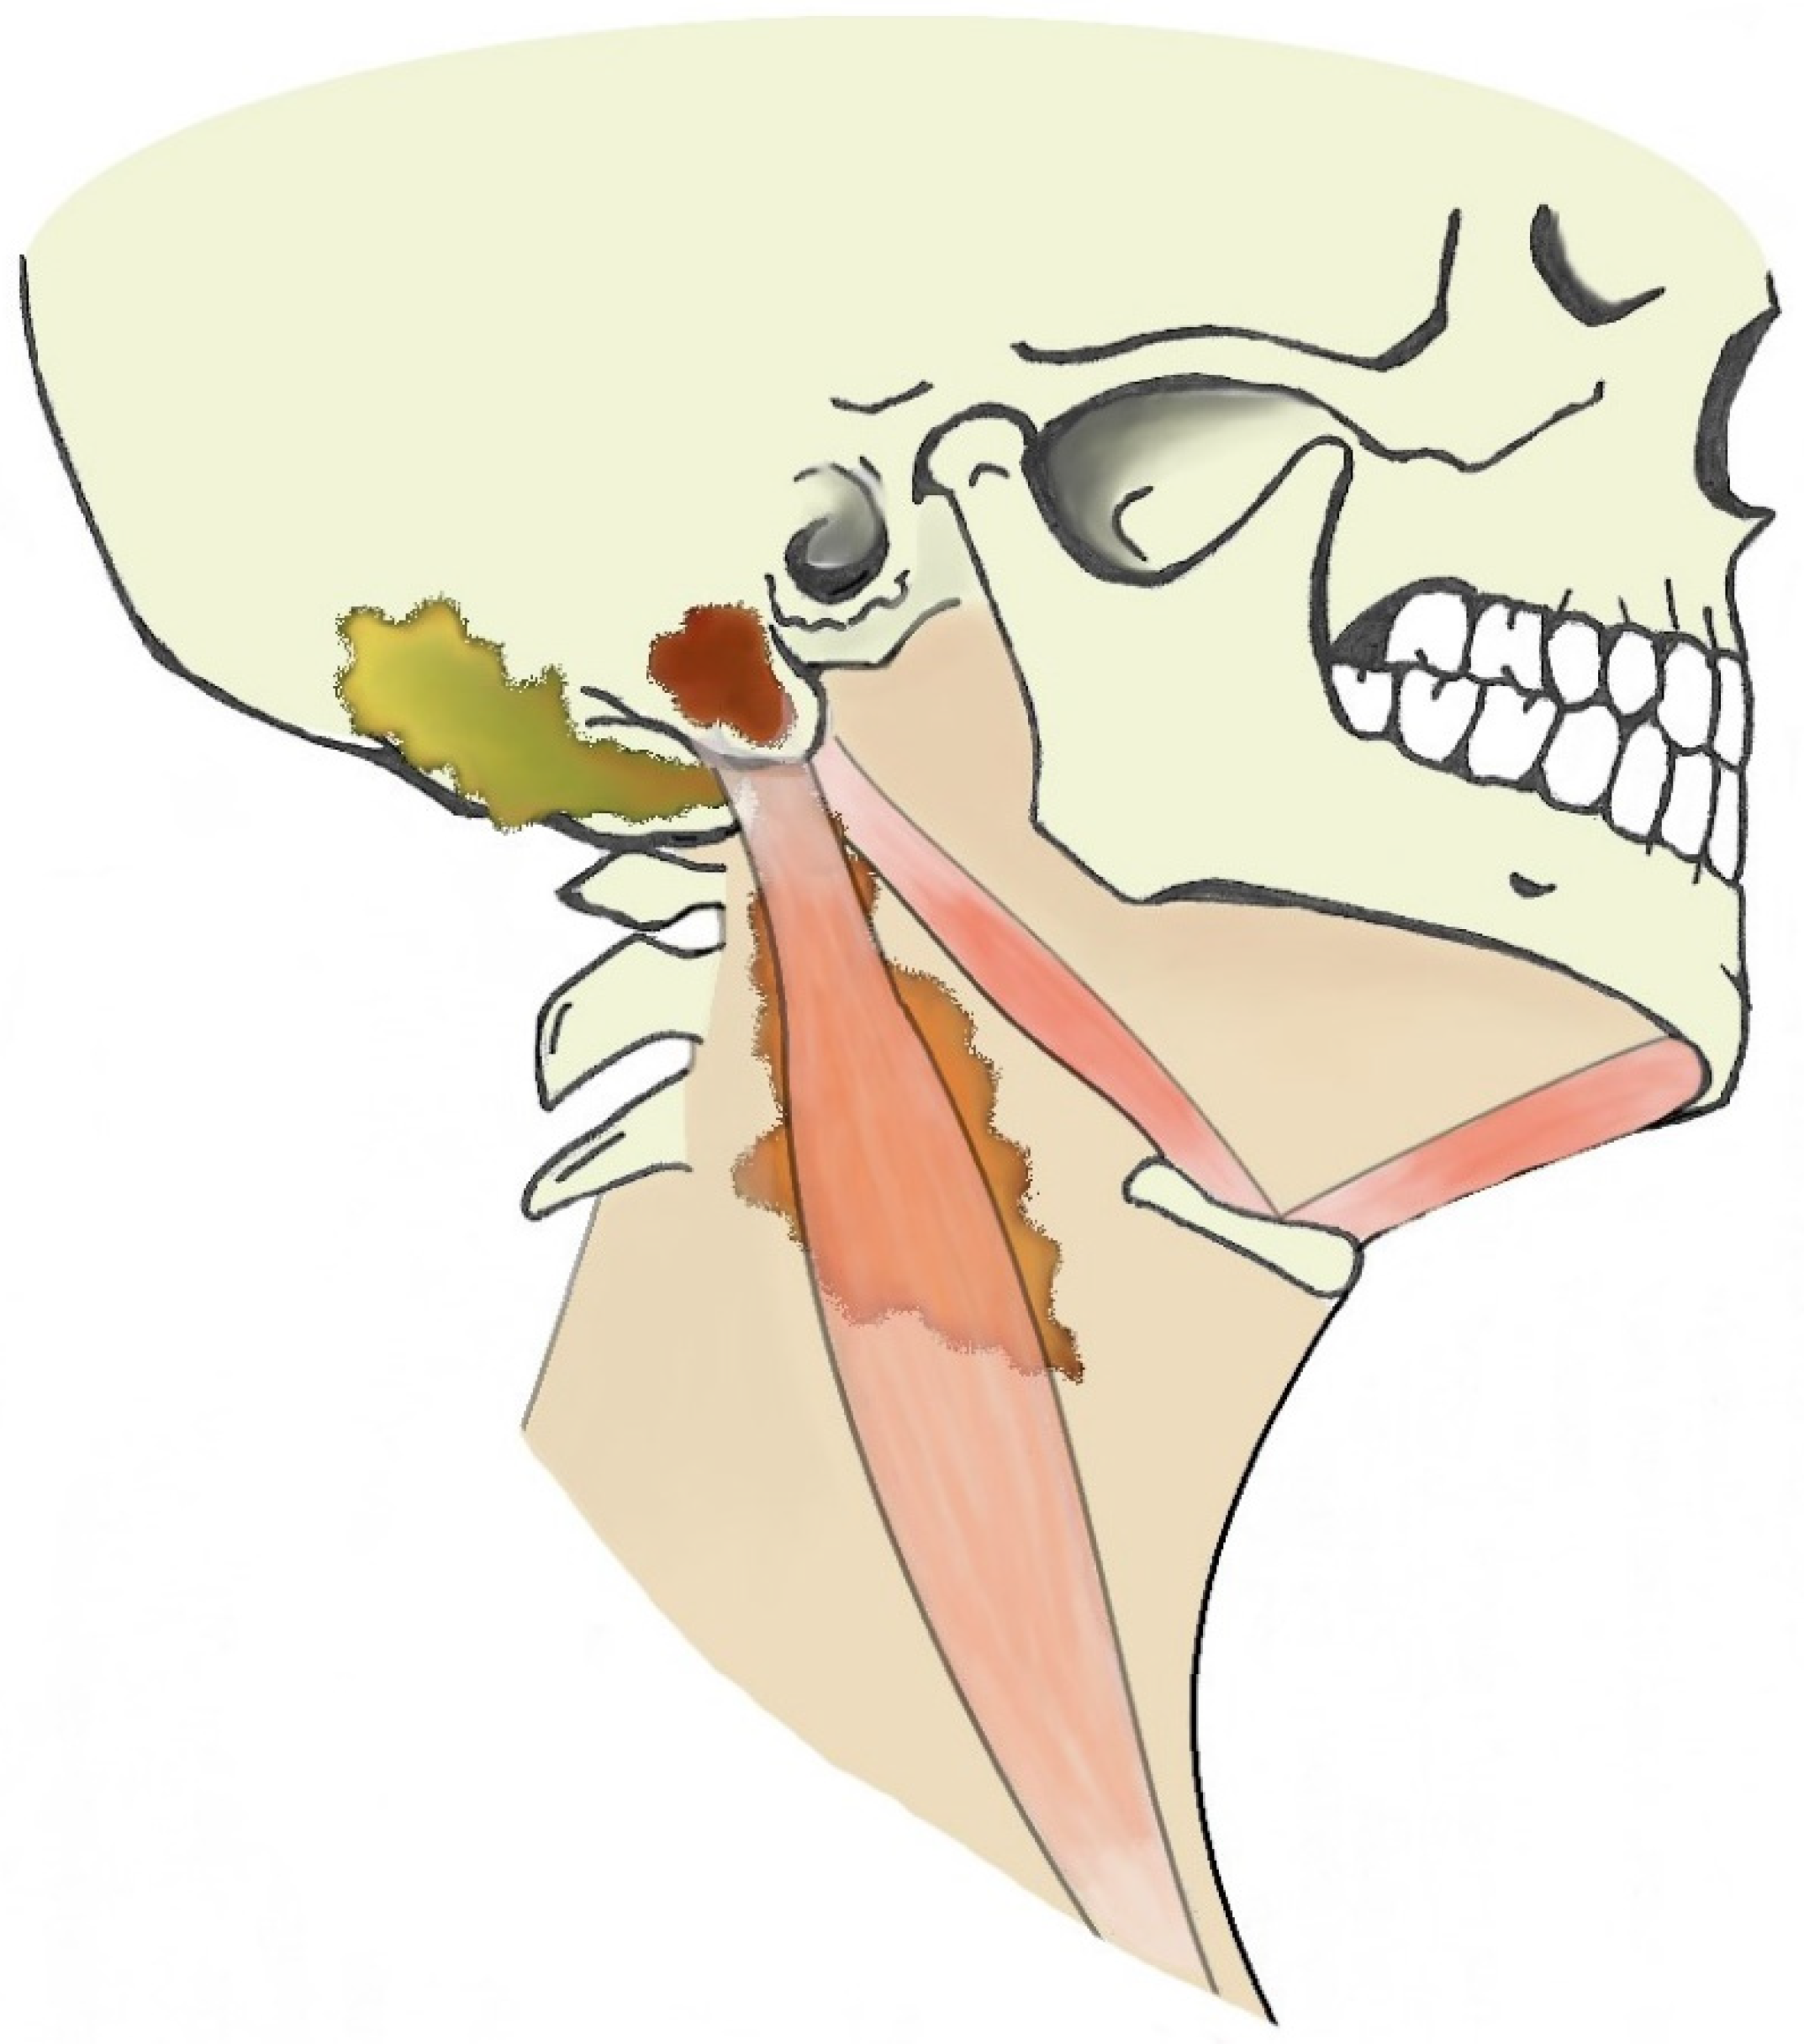

When dealing with suppurative processes originating from the mastoid bone, the diffusion pathway through the neck should be considered as this might be pivotal for subsequent evolution and for treatment planning. Suppurative processes from the mastoid might spread through bone erosion along three different paths: medial, lateral, or posteromedial [45]. Due to the complex anatomy of the several neck muscles and fasciae connected to the mastoid, the site of bone erosion will determine the subsequent diffusion path of the suppurative process that is eventually classified with different eponyms (Figure 3).

A bone erosion medial to the mastoid allows the pus to spread to the posterior cervical and perivertebral spaces, deep into the sternocleidomastoid muscle (Bezold’s abscess); a posteromedial bone erosion can result in pus spreading posteriorly to the insertion of the digastric muscle and in the occipital region (Citelli’s abscess); a bone erosion lateral to the mastoid can give origin to a subperiosteal empyema that usually reaches the surface in the peri-mastoid subcutaneous spaces. However, this strict classification might not be appropriate in case of neck anatomy variants, erroneous identification of suppurative diffusion processes or coexistence of multiple paths. In fact, literature reports cases of Bezold’s abscess concomitant to subperiosteal empyema [22,30,38,46,47,48,49], occurring after mastoid surgery (i.e., consistent with a postoperative complication [24]) or spreading into the occipital region [50,51]. A spread to retro-parapharyngeal spaces has also been described in literature [8,32,34,42,52].

Figure 3. Illustration of extracranial otogenic abscesses. Bezold’s abscess (orange), Citelli’s abscess (yellow), subperiosteal empyema (brown).